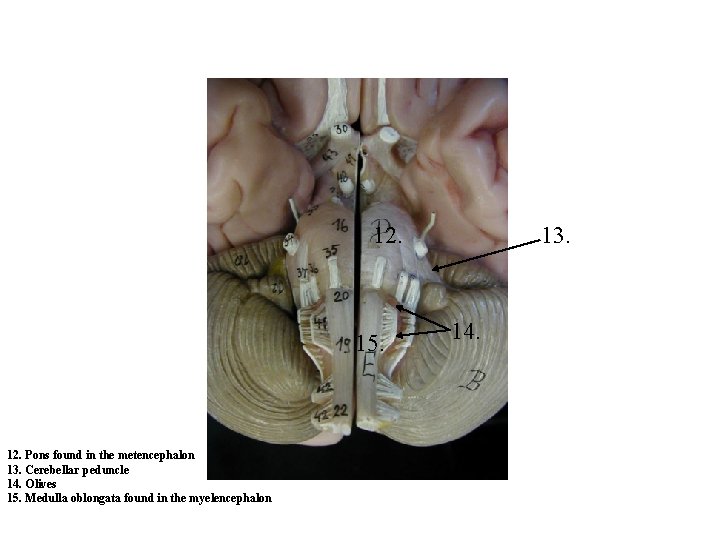

12. 15. 12. Pons found in the metencephalon 13. Cerebellar peduncle 14. Olives 15. Medulla oblongata found in the myelencephalon 13. 14.